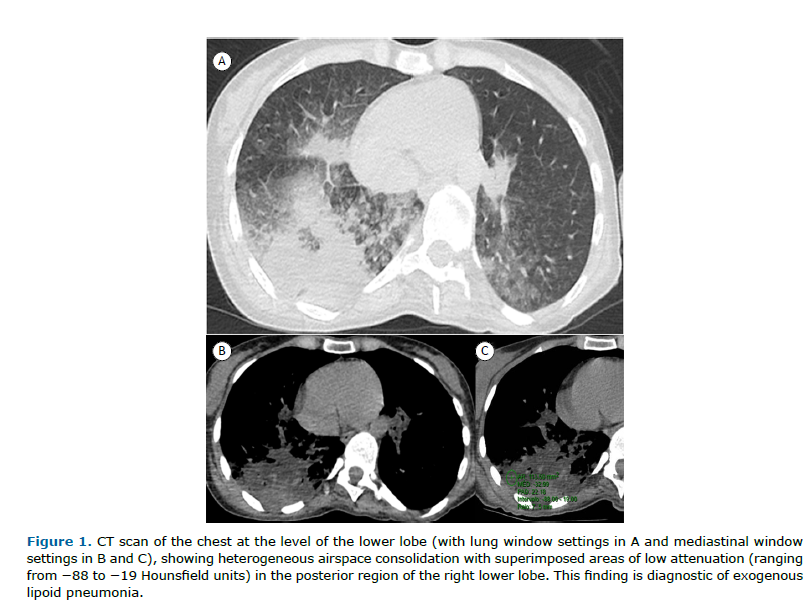

Here, we present the case of a 40-year-old woman who sought emergency care for abdominal pain and underwent abdominal CT examination, which showed opacities in the lung bases and prompted her referral to a pulmonologist. The patient had been diagnosed with multiple sclerosis at the age of 18. She had no significant respiratory symptom, reporting no cough, expectoration, dyspnea, or fever. Physical examination and laboratory test findings were unremarkable. Chest CT showed heterogeneous consolidation in the right lung with areas of interspersed fat density (careful measurement of density at different sites of consolidation showed negative densities, ranging from −12 to −88 Hounsfield units [HU]), consistent with lipoid pneumonia (Figure 1). History taking revealed that the patient had been using cannabidiol oil (10 drops taken orally twice a day) for approximately 2.5 years. She reported using no other oily or fatty substances. In addition, she reported choking when drinking liquids, as well as accumulation of mucoid secretions in the oropharynx. The final diagnosis was exogenous lipoid pneumonia (ELP).

The most common CT findings are airspace consolidations, ground-glass opacities, a crazy-paving pattern, interlobular septal thickening, airspace nodules, and mass-like lesions. However, none of these findings is a specific radiological feature of ELP. The most characteristic finding in patients with ELP is consolidation with areas of fat attenuation (i.e., negative attenuation values). However, the measured attenuation values may be higher than those of pure oil, given that the oil is spread within the affected parenchyma and mixed with components of pulmonary fibrosis and/or inflammatory exudates. Care must be taken when measuring these values in order to prevent a false-positive interpretation. These measures should be taken in the most hypodense part of the consolidation areas, free of any aerated parenchyma on the periphery or areas of air bronchogram, because of interferences caused by partial volume averaging of partly aerated lungs. Air and soft tissue, when averaged together, can mimic the characteristic attenuation values of fat. Low densities within consolidations may be due to areas of necrosis or fat. In areas of necrosis, although density measurements are low, they are usually positive. In areas with fat, density measurements are negative. Negative densities in lung lesions can be seen in nodules, masses, or consolidations. The differential diagnosis of nodules or masses containing fat is broad, unlike that of fat-containing consolidations, which, to our knowledge, have only been described in cases of lipoid pneumonia.(1-4) This is corroborated by several studies suggesting that negative density values between −150 HU and −30 HU within areas of consolidation are diagnostic of lipoid pneumonia, especially when associated with a history of exposure to oil.(2,5-7) Demonstration of macrophages containing fat vacuoles is necessary only when CT does not show negative densities interspersed with consolidations.